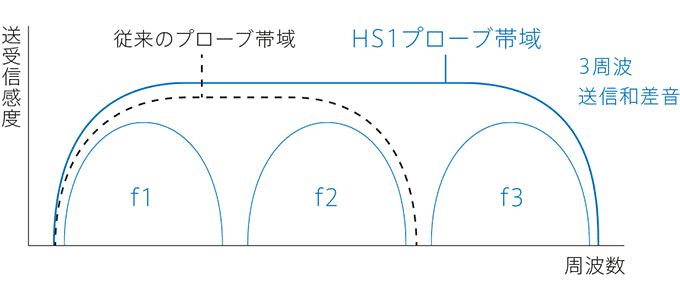

超広帯域プローブを最大限に活用するために、送受信技術の開発も必要でした。

そこで、コニカミノルタは、複数の周波数成分を合成送信するTriad-THI※技術を実用化しました。

これは、プローブ帯域内に含む全ての差音・和音成分を使ったイメージング技術であり、従来のTHIよりも、分解能とペネトレーションを高度に両立することを可能にしました。